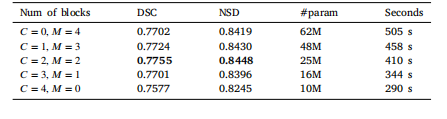

Table 5Ablation studies of model components. We present the performance of different combinations of CNN(C) and Mamba(M) blocks, alongside metrics ofparameter count, as well as the computational time per epoch.

表5 模型组件消融实验 我们展示了卷积神经网络(CNN,简称C)块与Mamba(简称M)块不同组合方式下的模型性能,同时提供了参数数量指标以及每个训练轮次(epoch)的计算时间。